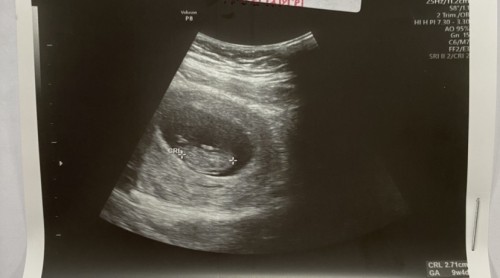

ตอนนี้เรา 9w5d อาการแค่ง่วงๆ อ่อนเพลีย คัดตึงเต้านม ทานได้อร่อยจนท้องอืดค่ะ ไม่มีปวดหน่วงท้องหรืออะไรเลย ปกติมั้ยคะ บางทีก็งงว่าตัวเองท้องใช่มั้ยนะ 🤣 ส่วนตัวฝากครรภ์ตอน7w เจอน้องและมีหัวใจเต้นแล้ว แต่ก็ตื่นเต้นทุกครั้งที่ซาวน์ ล่าสุดหมอนัดเสาร์นี้ 10w ใครมีภาพซาวน์มาอวดหน่อยค่ะ ตื่นเต้นมากกก ………. อัพเดทที่ไปซาวน์มาค่ะ หัวใจเต้นดี มีแขนขาดุ๊กดิ๊กๆ ได้ หมอบอกโตจากเดิมพอดี 3 วีคเป๊ะเลย ค่อยสบายใจหน่อยค่ะ สถานีต่อไปคัดกรองNIPT